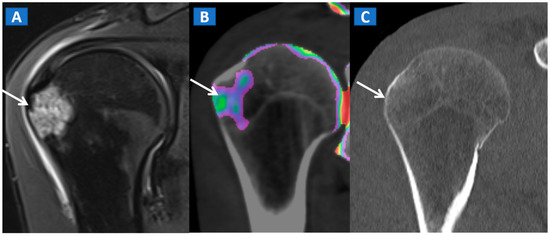

Figure 8.

A 35-year-old male with traumatic BME of the humeral head. On the coronal STIR MRI image (A), post-traumatic BME of the humeral head is depicted as a hyperintense signal in the subcortical area (arrow). The presence of BME is confirmed on the 2D DECT coronal 1 mm reconstructed image (B) (arrow). The high resolution 1 mm coronal CT image with bone window (C), rules out the presence of cortical fractures.

In the post-traumatic shoulder, DECT can identify BME of the humeral head, even in the absence of cortical fractures (Figure 8). Furthermore, in cases of anterior dislocation, CT images can be used for diagnosing Hill-Sachs and bony Bankart lesions.

In evaluating the elbow and wrist, the presence of BME as depicted by DECT, can assist the radiologist in identifying subtle meshed fractures. In addition, the ability of DECT to reduce metal artifacts may facilitate a more reliable evaluation of small anatomical structures, for example in cases of persistent pain after surgery, especially in patients where metallic hardware is present (Figure 9).